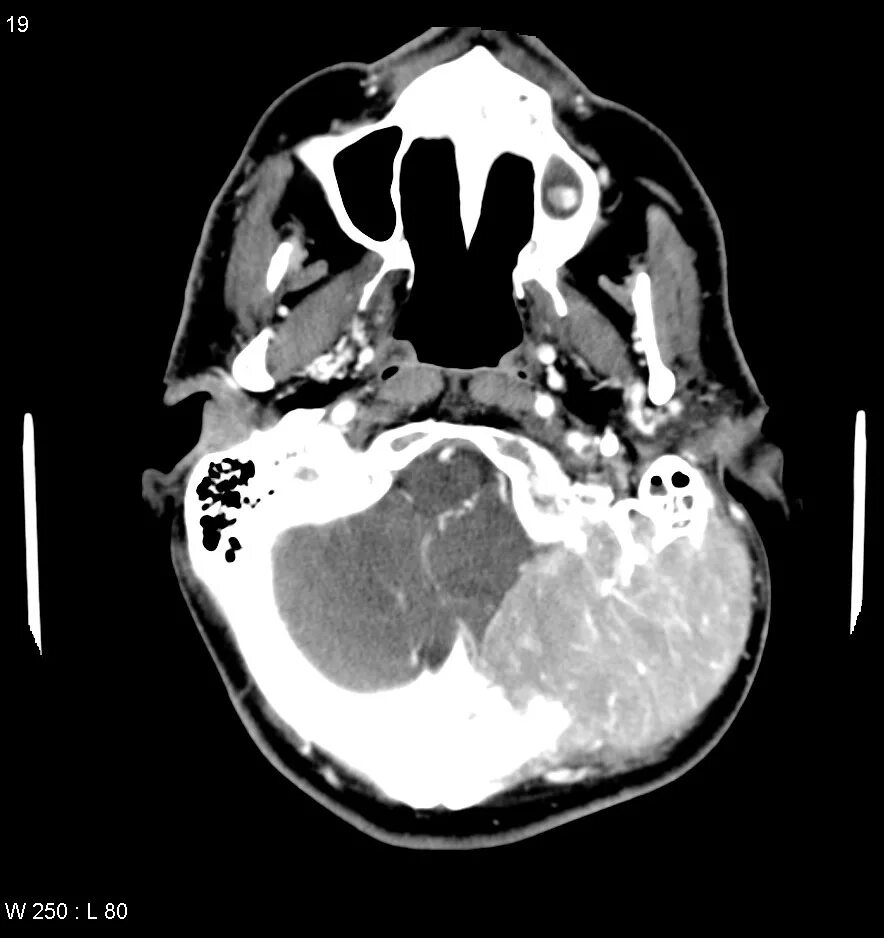

Череп на кт